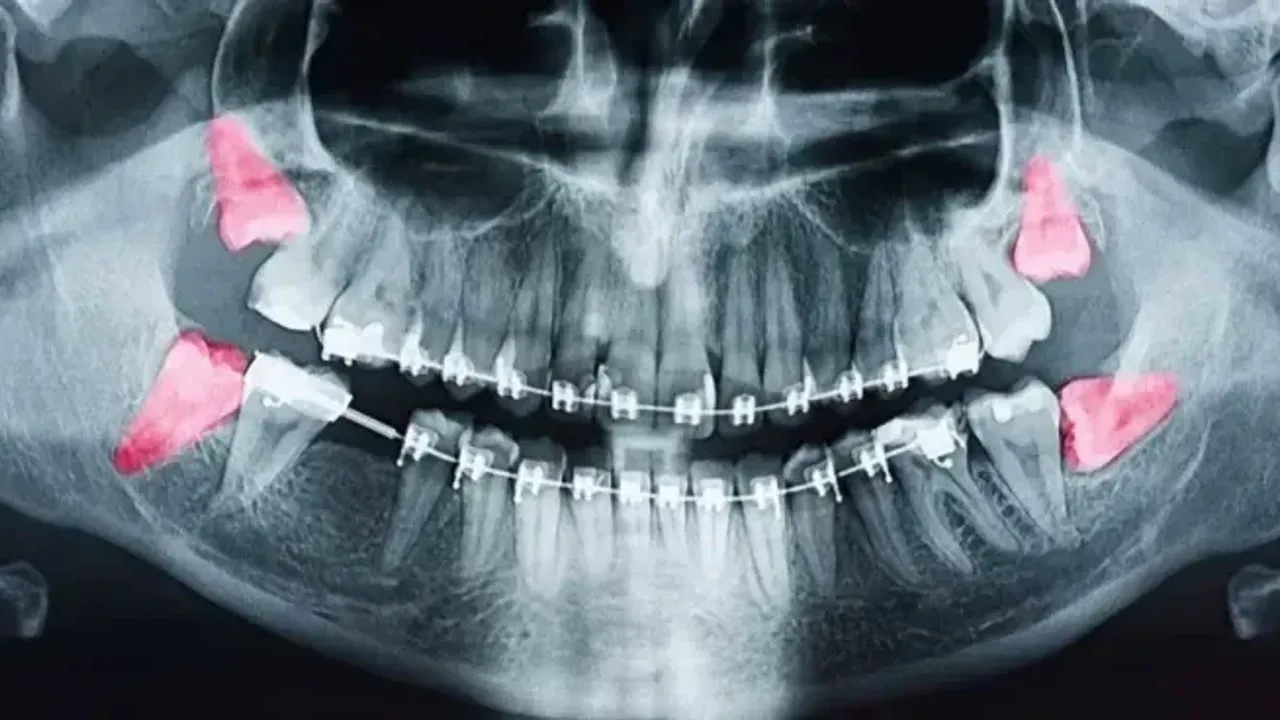

Yirmilik dişler bilinenin aksine yirmi yaşında çıkmak zorunda değildir. Toplamda dört adet olarak buluna bu dişler, on yedi yaşından, yirmi beş yaşına kadar oluşabilir. Eğer bu yaş aralığında yirmilik diş çıkmaz ise bu durum yirmilik dişlerin olmadığı anlamına gelmez. Çoğu zaman gömülü kalan bu dişler, herhangi bir ağrıya neden olmadığı sürece fark edilmeyebilir. Bu gibi durumlarda gömülü yirmilik yaş dişlerinin durumu, rutin diş muayenelerinde çekilen röntgen ile görüntülenebilir.

Yirmilik diş ağrıları ve diğer semptomları yaşayan kişilere yapılan muayenenin ardından genellikle diş röntgeni çekilir. Bu röntgen ile tüm dişlerin kökleri, kemik yapıları, açıları ve gömülü yirmilik dişler net bir şekilde görülür. Dışarıdan görülmeyen yirmilik dişler genellikle yatay olarak çıkar. Bunun yanı sıra yarı gömülü olacak şekilde gelişen yirmilik dişlere de çok sık rastlanmaktadır.

Bazı durumlarda gömülü yirmilik dişler, bulunduğu bölgede enfeksiyona neden olabilir. Bunun yanı sıra kist oluşumları da yine yirmilik dişlerin gömülü olmasından dolayı meydana gelir. Bu gibi durumlarda diş çekiminden önce durumun düzeltilmesi için ilaç tedavisinin başlatılması uzman hekimler tarafından önerilir.